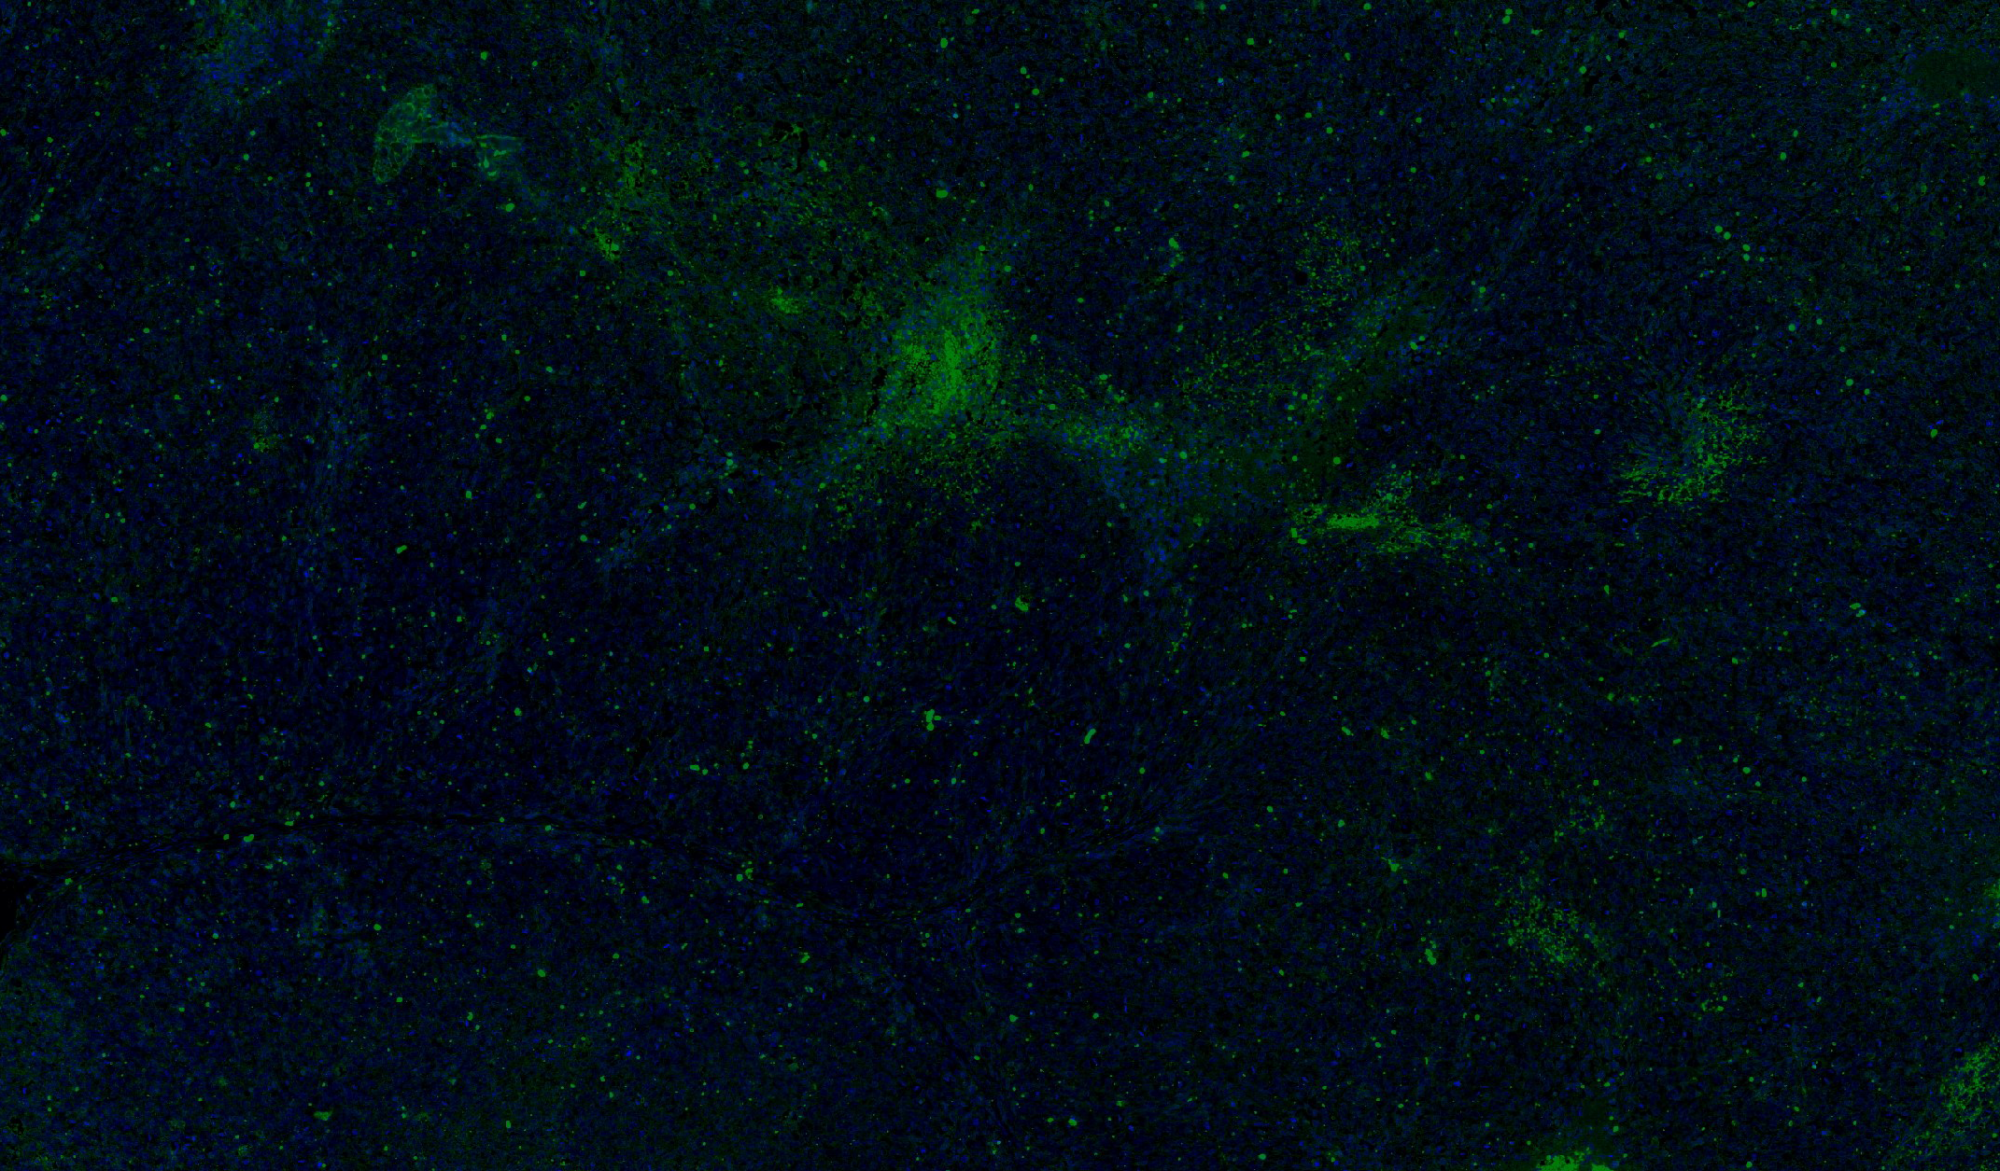

病理平臺(tái)可承接:石蠟切片,切片掃描,熒光掃描,HE染色,各種特殊染色,如:Masson、油紅O、PAS、番紅O、ALP、TRAP、甲苯胺藍(lán)以及免疫組化/熒光、原位雜交等,3D HISTECH滿足對(duì)結(jié)果高質(zhì)量,高標(biāo)準(zhǔn),周期快的實(shí)驗(yàn)外包需求,并提供染色培訓(xùn)服務(wù),分線上視頻,線下實(shí)操帶教兩種培訓(xùn)方案。

案例展示

組織染色實(shí)驗(yàn)室